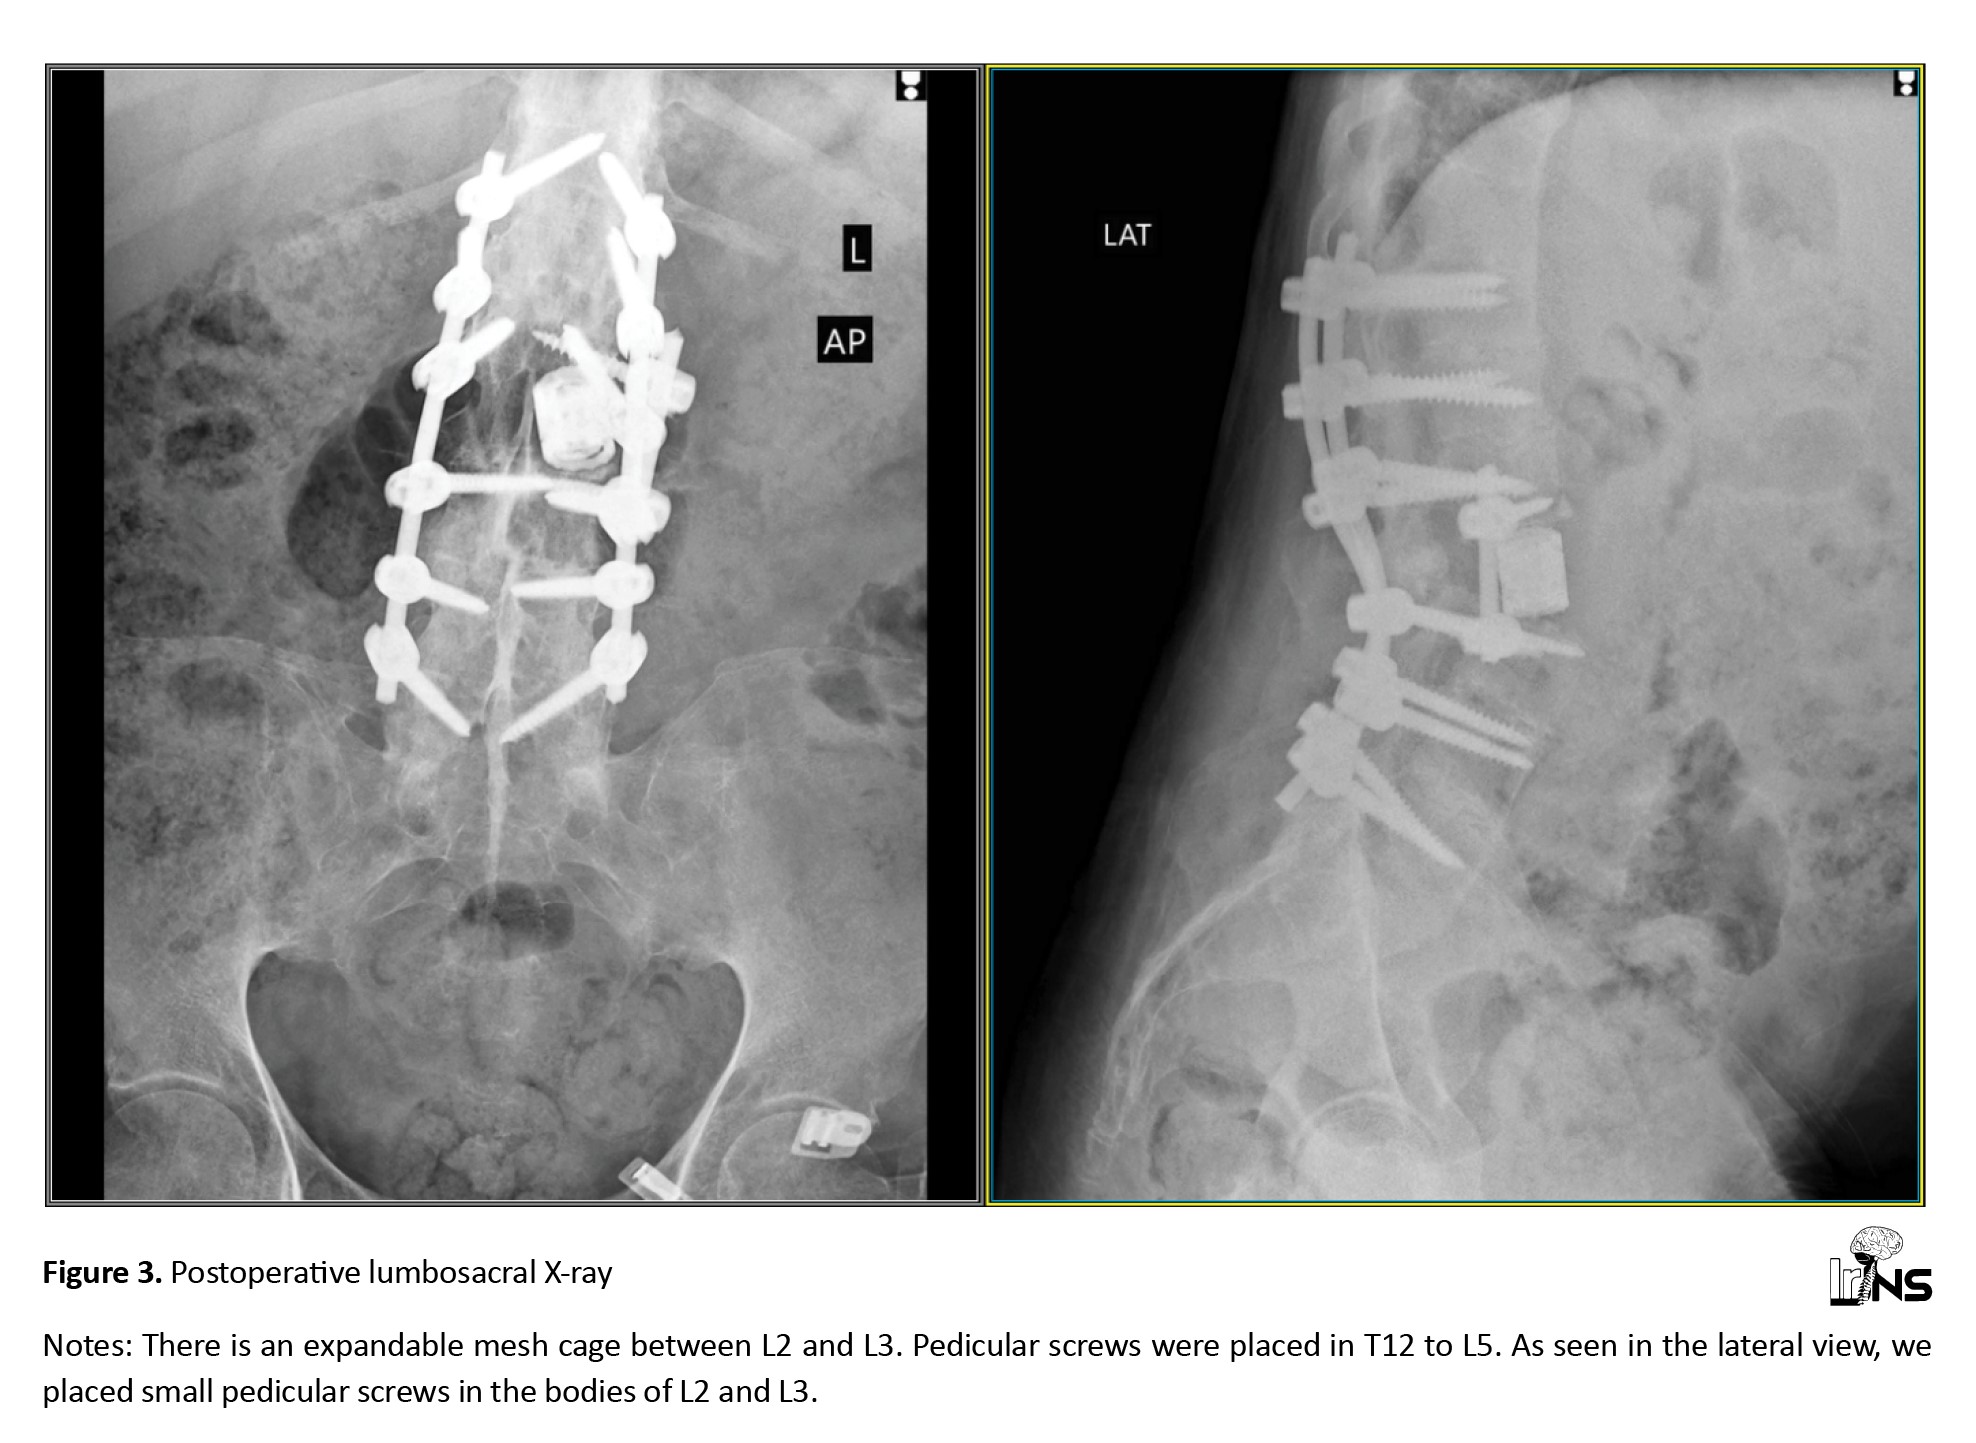

Second stage: The patient was placed in a lateral position (left side up) with meticulous caution and under IONM. Next, we localized the incision site under C-arm guidance and used a retroperitoneal corridor to reach the L2-L3 region from the left side. Then we placed an expandable cage in the gap created by trauma between L2 and L3. For further stabilization, we used a 4×25 mm screw and inserted it into the L2 and L3 vertebrae through the lateral side of the body. Then, a rod was placed, further stabilizing the cage in the anterior column. IONM did not show any change in MEP and SSEP.

Figure 3 shows the patient’s postoperative image.